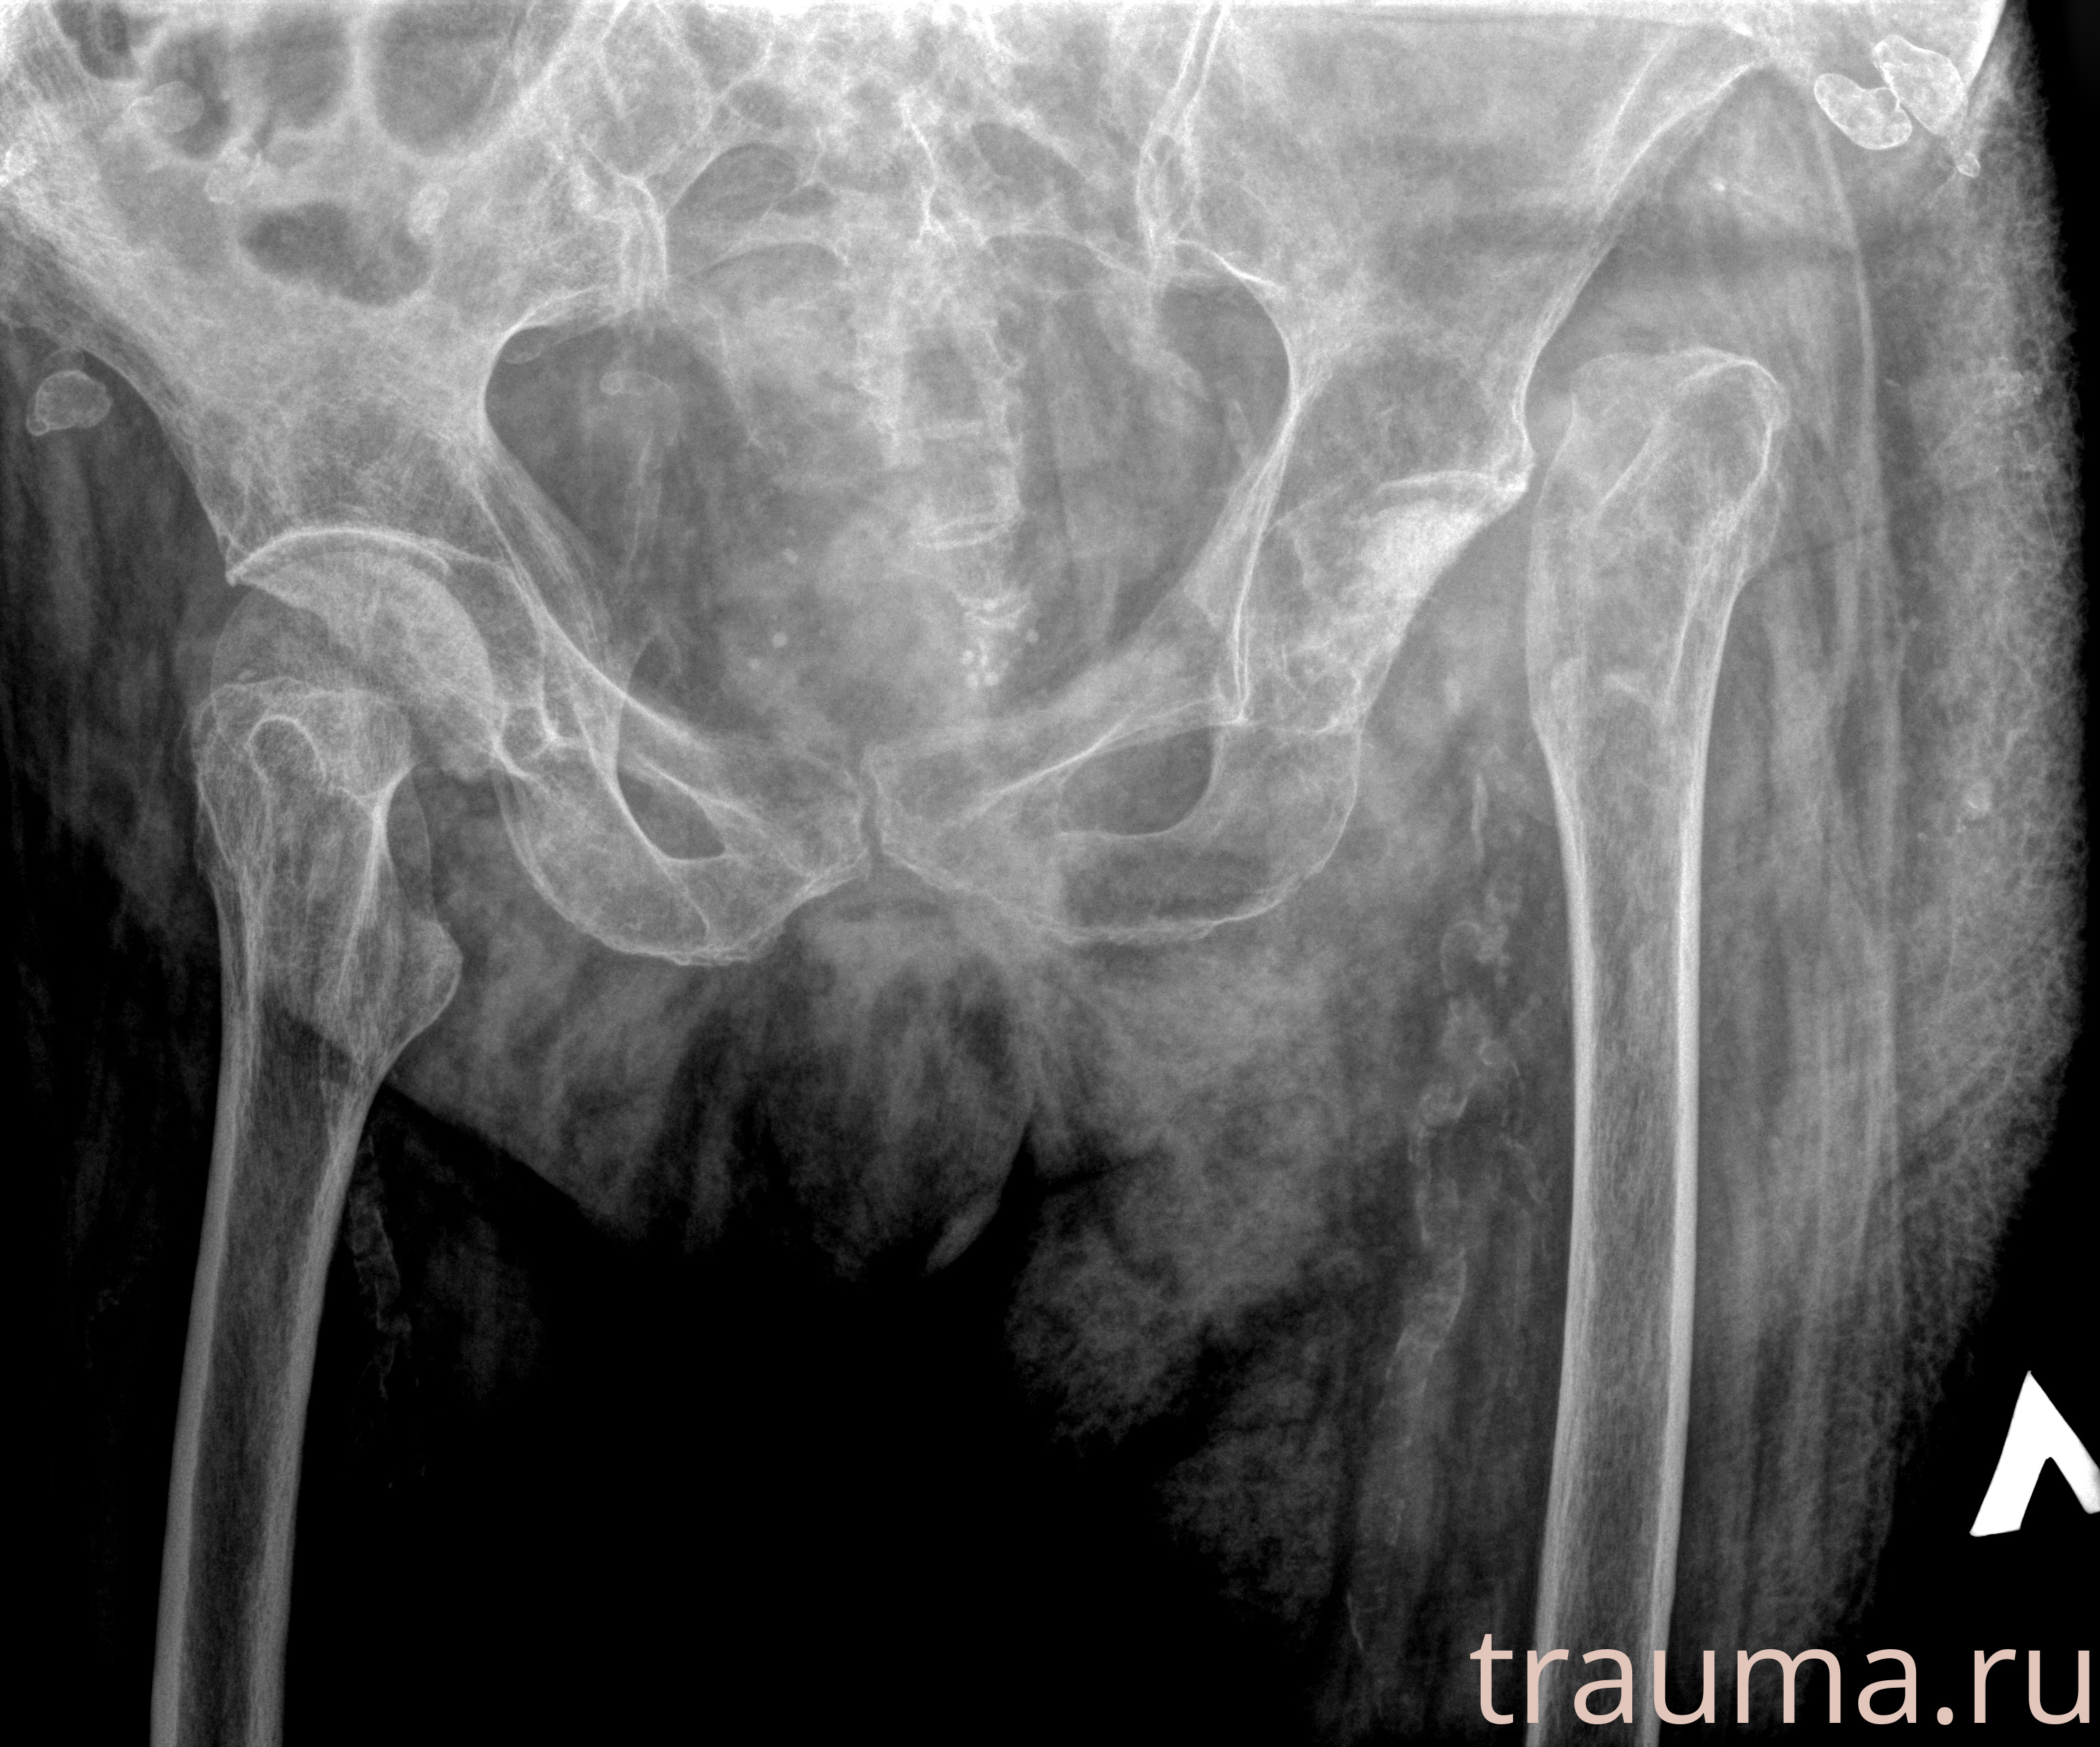

Первая помощь при переломе шейки бедра

Рентген на дому: по вашему адресу приезжает врач-рентгенолог, травматолог-ортопед с мобильным рентгеновским аппаратом, проводит диагностику травмы или заболевания, делает необходимые рентгенограммы, дает рекомендации по дальнейшему лечению. Получить качественные снимки в домашних условиях возможно благодаря уникальной методике, разработанной МосРентген Центром для института  Склифосовского